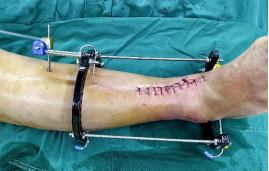

1.CO外固定半環(huán)連接跟骨穿針并通過CO接骨機器人配套的連接桿與CO接骨器人中間機械臂相連,調(diào)整機械臂,進(jìn)行骨折端初步復(fù)位,C臂確認(rèn)復(fù)位滿意,關(guān)節(jié)間隙拉開。

連接CO接骨機器人

牽拉復(fù)位

2.CO接骨機器人持續(xù)牽引維持復(fù)位,選擇前外側(cè)切口對前外側(cè)骨塊進(jìn)行撬撥復(fù)位,并用克氏針進(jìn)行臨時固定。C臂透視復(fù)位滿意,放置兩塊鋼板進(jìn)行固定。

3.在脛骨近端穿入一根克氏針,連接CO外固定架進(jìn)行固定,并外踝處穿入一根克氏針進(jìn)行固定。C臂透視位置滿意,縫合結(jié)束手術(shù)。